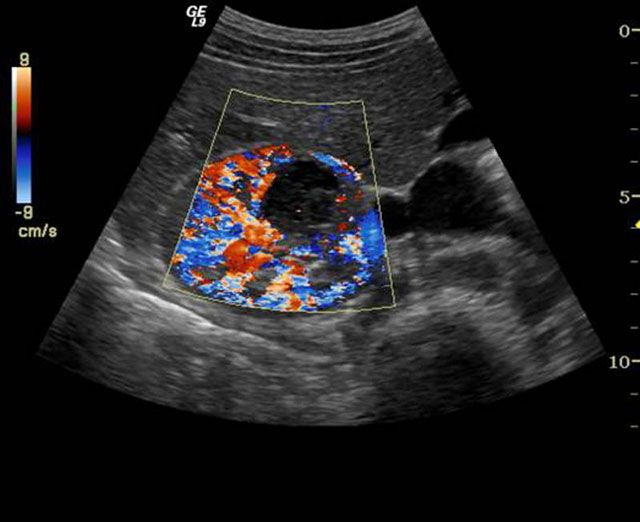

Με τη χρήση της κεφαλής αυτής επιτυγχάνεται ο εντοπισμός και διάγνωση μικρών όγκων, καθώς και η ανίχνευση ανώμαλων νεόπλαστων αγγειακών δομών. Ενσωματώνει τη μοναδική επαναστατική πλατφόρμα υπερηχοτομογραφίας Truscan, η οποία καθιστά δυνατή την αποθήκευση των αυθεντικών ακουστικών δεδομένων (digital raw data) για πλήρη και πραγματική μεθ’ επεξεργασία των διενεργούμενων εξετάσεων, ώστε να δίδεται η δυνατότητα στον ιατρό να μελετά διεξοδικά τις υπερηχογραφικές εικόνες σε δεύτερο χρόνο, χωρίς να επιβαρύνεται και να ταλαιπωρείται ο ασθενής.

• Νεφρών